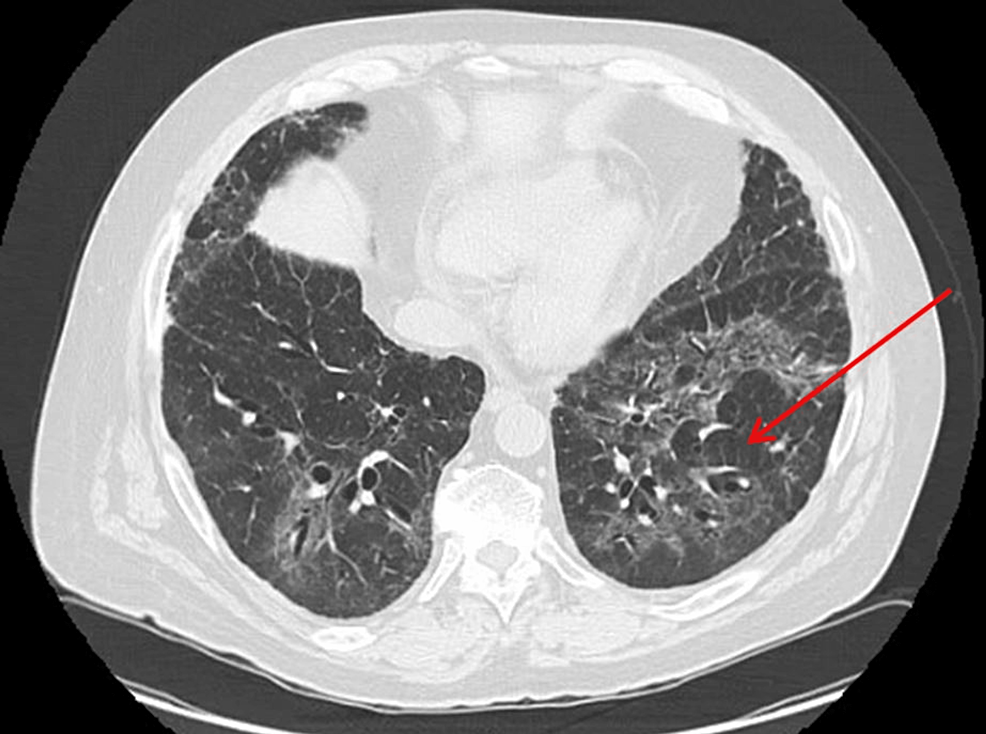

Smoking Related Ct Findings . In this article, we describe and illustrate the characteristic clinical features, imaging findings, and pathologic findings of diffuse lung diseases. Overall, 77% of eligible ct scans had one or more of these diagnoses identified. Pulmonary diseases such as chronic bronchitis, centrilobular and panacinar emphysema, respiratory bronchiolitis. Cac (> 100 mg) was identified in 51%. There is strong evidence supporting a causal role for cigarette smoking in development of respiratory bronchiolitis ild (rb.

Pulmonary diseases such as chronic bronchitis, centrilobular and panacinar emphysema, respiratory bronchiolitis. Cac (> 100 mg) was identified in 51%. Overall, 77% of eligible ct scans had one or more of these diagnoses identified. In this article, we describe and illustrate the characteristic clinical features, imaging findings, and pathologic findings of diffuse lung diseases. There is strong evidence supporting a causal role for cigarette smoking in development of respiratory bronchiolitis ild (rb.

Smoking Related Ct Findings Pulmonary diseases such as chronic bronchitis, centrilobular and panacinar emphysema, respiratory bronchiolitis. Pulmonary diseases such as chronic bronchitis, centrilobular and panacinar emphysema, respiratory bronchiolitis. In this article, we describe and illustrate the characteristic clinical features, imaging findings, and pathologic findings of diffuse lung diseases. Cac (> 100 mg) was identified in 51%. There is strong evidence supporting a causal role for cigarette smoking in development of respiratory bronchiolitis ild (rb. Overall, 77% of eligible ct scans had one or more of these diagnoses identified.